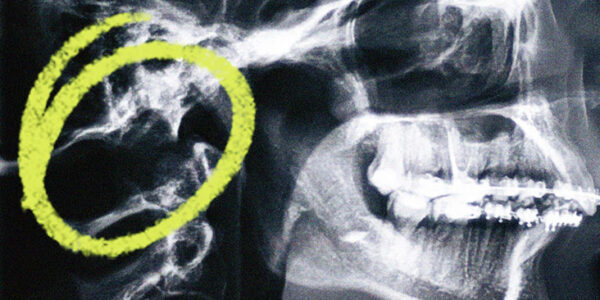

¿Qué es la malformación de Chiari?

La malformación de Chiari es un grupo de defectos que afectan el cerebro y el canal espinal. El cráneo puede ser demasiado pequeño o deforme, lo que hace que el tejido cerebral se extienda hacia el canal espinal. Puede causar…